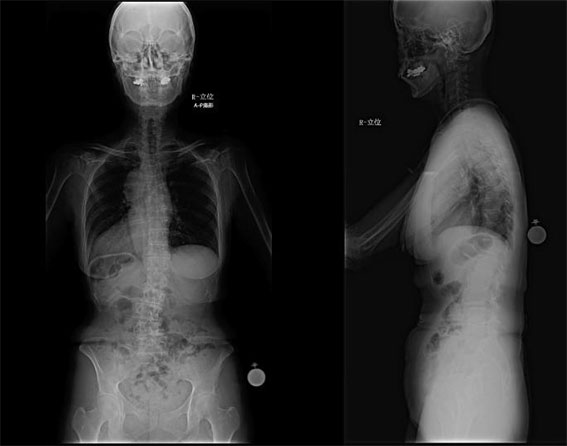

【図1】 術前の脊椎全長写真

体に懐中時計のような形をしたマーカーを装着し、脊椎全長のX線写真を撮影して脊椎の形状を記録します。

【図2】 UNiDTM ASIによるプランニング

脊椎の変形をコンピューター上で計測・解析し、脊椎変形矯正のプランニングを行います。

そのシミュレーション結果に基づき、脊椎変形を矯正するための患者様の状態に適したロッド形状を決定します。